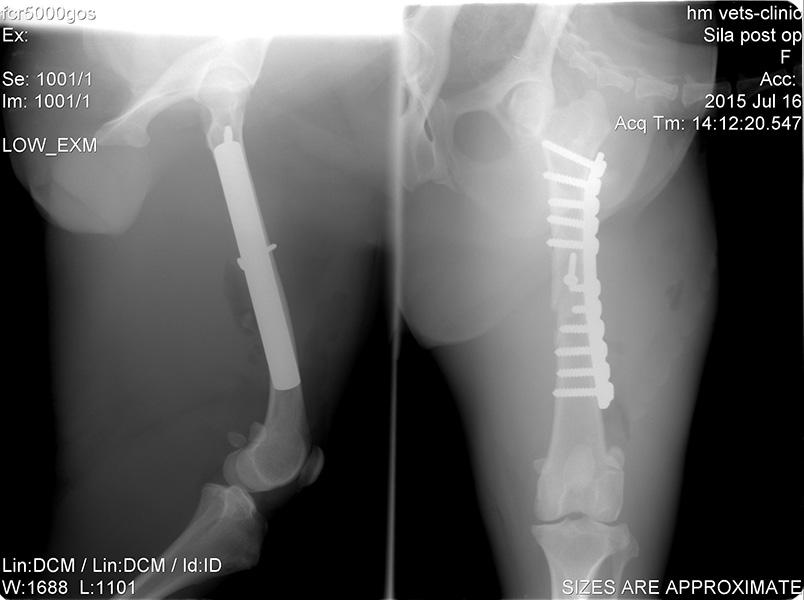

Ορθοπεδική

Ορθοπεδική

Το κτηνιατρείο hm vets αναλαμβάνει ψηφιακή ακτινογραφία, έλεγχο δυσπλασίας ισχίου, ορθοπεδική-νευροχειρουργική, χειρουργική μαλακών μορίων, οφθαλμολογία, εσωτερική παθολογία και εργαστηριακές εξετάσεις (αίματος, βιοχημικές, ανοσολογικές, ορμονολογικες, μοριακές και ιστοπαθολογικές).

Το κτηνιατρείο hm vets αναλαμβάνει ψηφιακή ακτινογραφία, έλεγχο δυσπλασίας ισχίου, ορθοπεδική-νευροχειρουργική, χειρουργική μαλακών μορίων, οφθαλμολογία, εσωτερική παθολογία και εργαστηριακές εξετάσεις (αίματος, βιοχημικές, ανοσολογικές, ορμονολογικες, μοριακές και ιστοπαθολογικές).